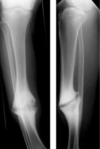

Spiral Fractures

Fracture line is

rotated around the

longitudinal axis of

the bone

The length is at

least twice as long

as the width of the

bone involved